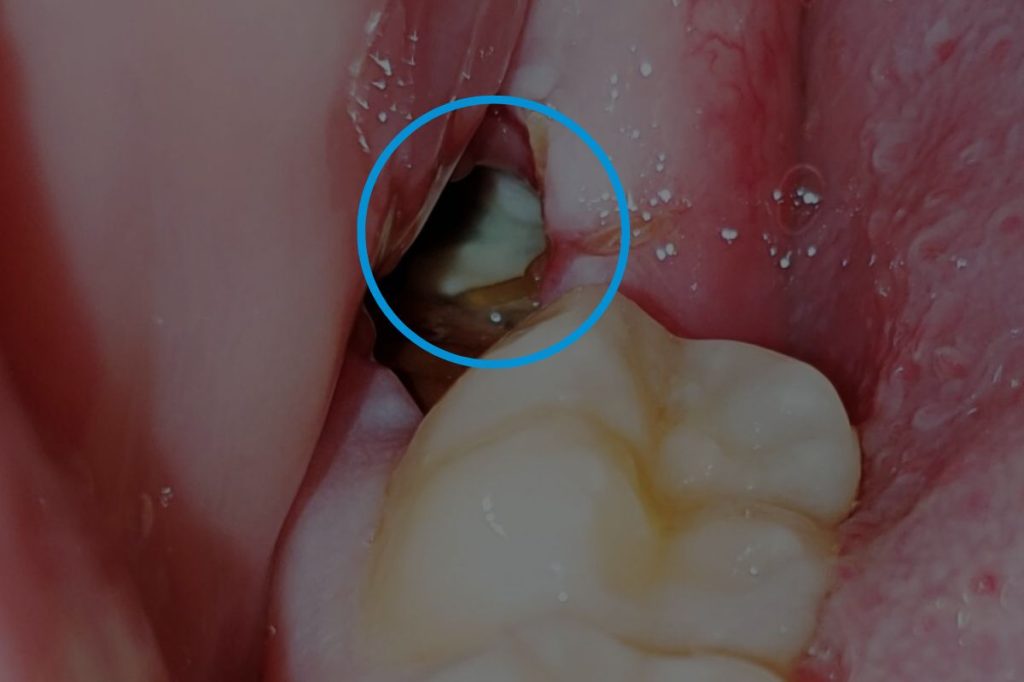

After Extraction of Wisdom Teeth